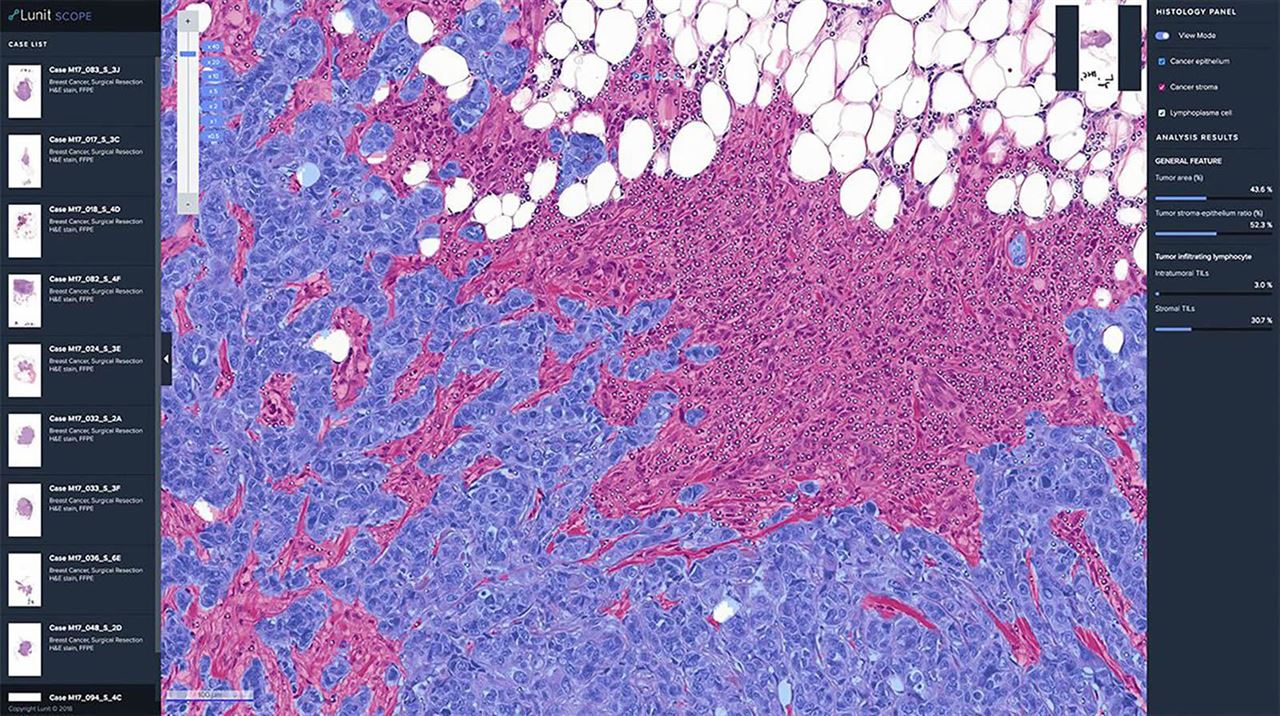

직관적으로 말하자면 효과적인 진단과 치료에 도움을 주는 서비스와 제품 개발이 루닛이 하고 있는 일입니다. 영상진단에 도움을 주는 루닛 인사이트(Lunit INSIGHT) 제품군과 항암제에 대한 치료 반응을 예측해 주는 루닛 스코프(Lunit SCOPE) 제품군입니다.

두 번째, 효과적인 치료를 위해서는 인공지능으로 항암 치료제에 대한 반응을 정확하게 예측해주는 루닛 스코프(Lunit SCOPE)를 연구개발하고 있습니다.

향후 계획을 묻는 질문에 루닛측은 궁극적으로 AI가 암·질병 여부를 판단해서 진단하는데 그치지 않고, 환자의 데이터·유전자 정보를 분석해 최적의 항암제를 추천해 주는 치료 영역으로 AI를 적용할 계획이라고 전했습니다.

이는 암 환자에게 적합한 항암제를 맞춤형으로 선택해 환자의 생명에 도움을 줄 수 있다는 것이죠. 또한 제약업체들이 신약 개발을 할 때 드는 상당한 시간과 비용을 상당부분 절감할 수 있을 것이라 말했습니다.